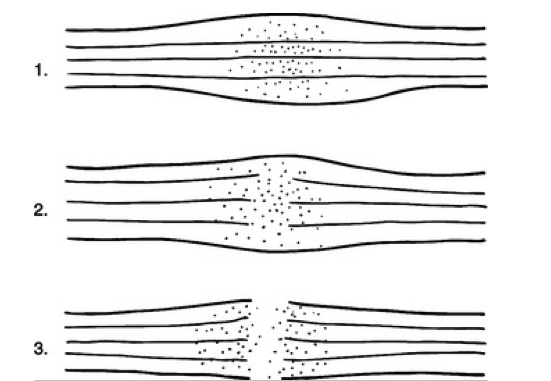

Phân độ tổn thương dây thần kinh ngoại biên thường dùng nhất là phân loại của Seddon (năm 1943), chia làm 3 mức độ:

- Neuropraxie: các axon chỉ bị ức chế, chức năng của chúng chỉ đình chỉ tạm thời.

- Axonotmesis: là các axon bị đứt cùng với các bao myêlin của chúng, nhưng vẫn còn lớp perineurium

- Neurotmesis: các bó sợi thần kinh bị đứt rời hẳn. Không thể có hồi phục tự nhiên; cần phải mổ nối lại dây thần kinh.

Một phân loại khác chia tổn thương thành 5 độ (Phân loại của Sunderland, 1968), nhưng vì phức tạp hơn nên tôi không trình bày ở đây.